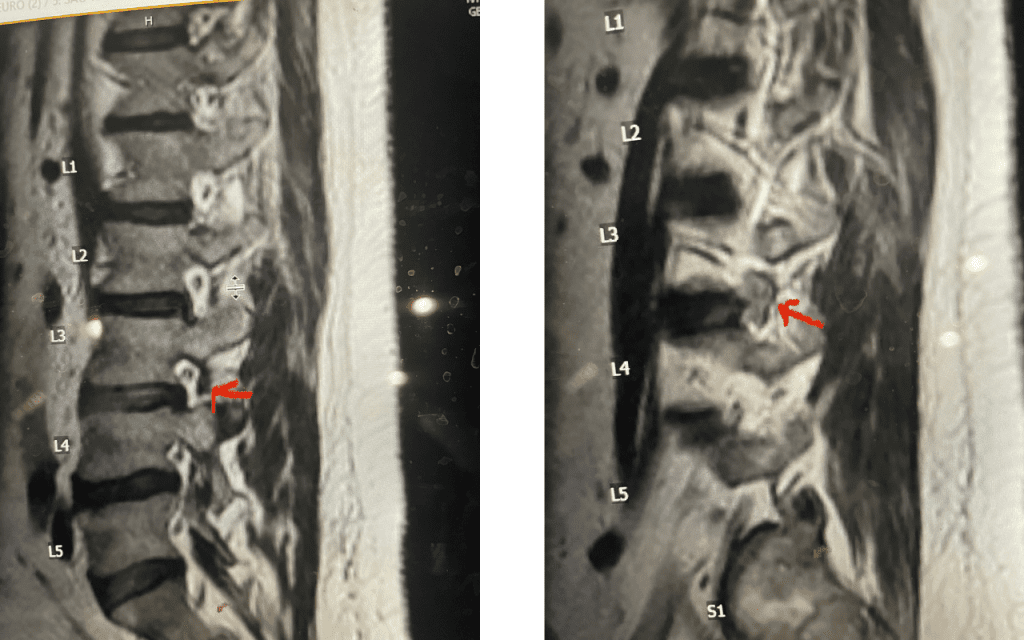

Fig 9: Axial and Sagittal T2-weighted lumbar MRI demonstrating left L4-5 far lateral disc herniation (red arrow). Notice how on the sagittal MRI the disc herniation fills the foramen and is superiorly oriented, compressing the left L4 nerve root against the L4 pedicle (blue arrow).